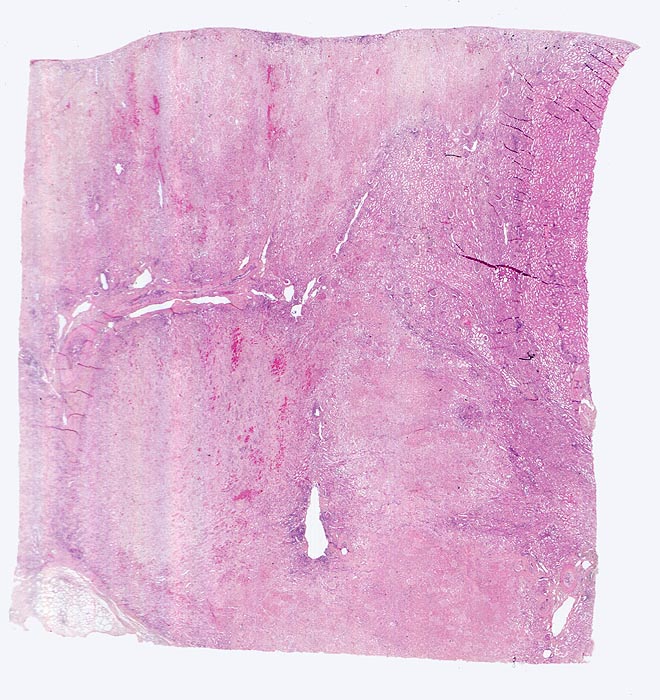

akuter Niereninfarkt

Ausgedehnte anämische Nekrose mit aufgehellter verwaschener Struktur. Stellenweise ist ein hämorrhagischer Randsaum erkennbar. Ein sehr schmaler Saum von vitalem Parenchym ist an der Rindenoberfläche dank Kollateralen aus der Nierenkapsel erhalten. Anschnitt einer Arteria arcuata mit rekanalisiertem Verschluss.

Chronisches Vorhofflimmern mit Morbus embolicus: anämische Infarkte verschiedenen Alters in beiden Nieren und in der Milz. Alte abgebaute Enzephalomalazie im Versorgungsbereich der Arteria cerebri media rechts.

Das vorliegende Präparat wurde nicht senkrecht zur Nierenoberfläche zugeschnitten. Deshalb erscheint die Anordnung von Mark und Rinde etwas ungewöhnlich.